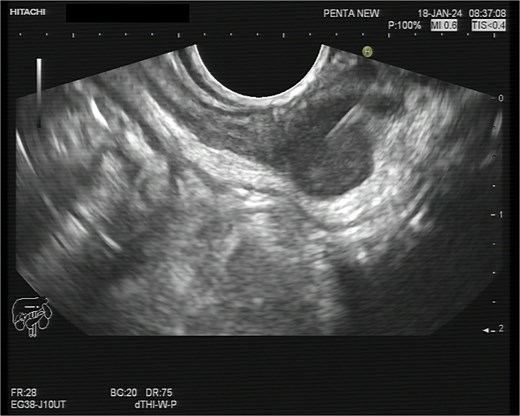

A 75-year-old woman with a past surgical history of serous papillary ovarian carcinoma underwent complete debulking surgery and adjuvant chemotherapy treatment 2 years prior to her current presentation. During follow-up, increased FDG uptake along with a 1.2-cm mass was seen on a PET-CT on the serosal surface of the recto-sigmoid junction (Fig. 1). An attempt was made to evaluate the lesion using trans-rectal sonography. Radial sonographic view showed a 12 mm, hypoechoic, well-defined lesion located at the serosal surface of the recto-sigmoid junction (Fig. 2). After reverting to a linear view, the lesion was sampled with fine-needle biopsy (Fig. 3) and whitish thick cores were retrieved (Fig. 4). The procedure was uneventful and no adverse events were noted. Pathology revealed fragments of high grade serous carcinoma of tubo-ovarian origin. Relying on the histological information gained from the biopsy, it was known that the lesion although not obvious to the eye during surgery, had to be found and resected. The surgical procedure was challenging with multiple adhesions, which made it difficult to locate the lesion. Based on the valuable preoperative knowledge, the patient was able to have a complete debulking of the tumor mass.

Radial sonographic view of the malignant lesion at the 2 o'clock position.

Linear view of the malignant lesion seen as a hypoechoeic mass with biopsy needle inside.